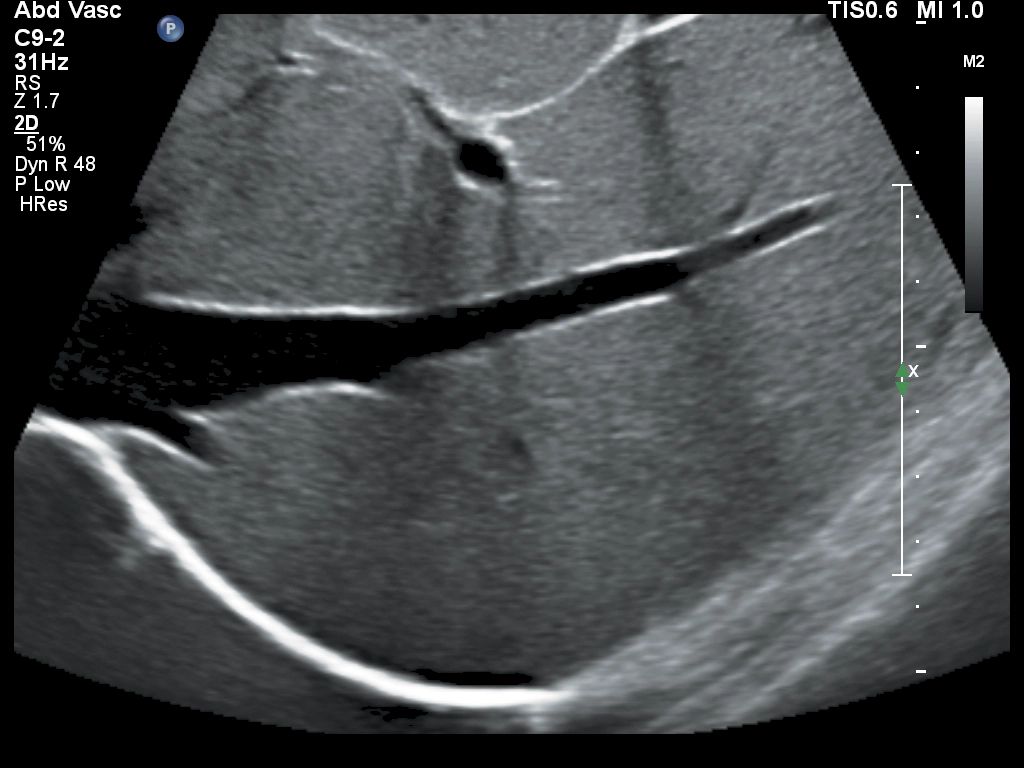

- Абдоминальные исследования

- Сосудистые исследования

Функции для исследования сосудов

- VPQ (Vascular Plaque Quantification) - функция автоматического количественного анализа атеросклеротических бляшек в сонной артерии в режиме 3D. Функция автоматически вычисляет количество бляшек, площадь просвета сосуда и идеально подходит для полноценного анализа состава атеросклеротических бляшек

- IMT - функция для автоматического расчета комплекса интима-медиа

- ROI - технология для согласованности и надежности акустических измерений для более простого анализа зоны интереса при контрастной визуализации, TDI и цветового допплеровского сканирования.

- Auto Doppler - автоматическая настройка импульсно-волнового допплера и ЦДК